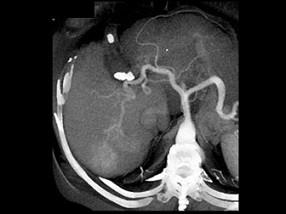

问题 男,44岁,患乙肝多年,现腹痛,腹胀,AFP增高,消瘦、乏力,影像检查如图,最可能诊断是 ( )

选项 A、肝硬化、肝癌 B、肝结节性增生 C、肝腺瘤 D、肝转移瘤 E、肝血管瘤

答案 A